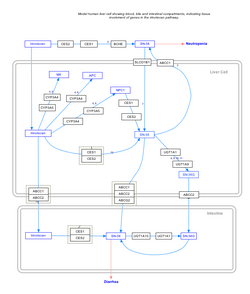

imgi_153_250px-IrinotecanPathway_WP229.png